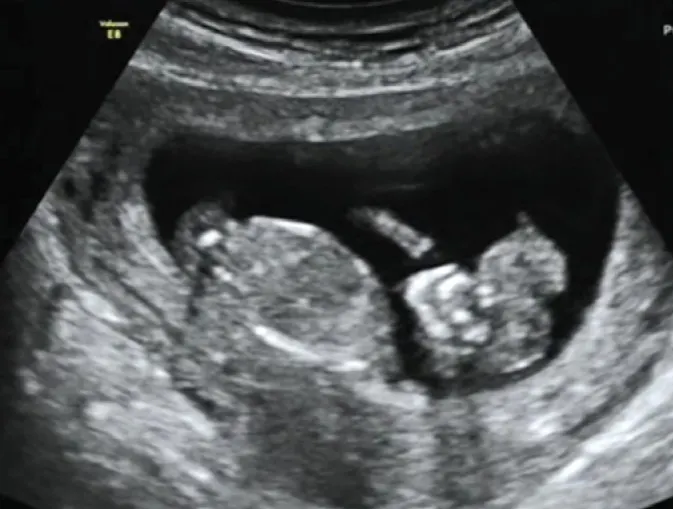

- 超音波finding(第一孕期)

羊水混濁(increased echogenecity of amniotic fluid):在羊水裡消失的腦組織造成的,也會有羊水過多的現象

Mickey mouse sign:雙葉型的腦組織

Beret sign:裸露的腦組織因為無顱骨的包覆,往前突出,可區分exencephaly與anencephaly

頭臀徑會比預期的週數還要小

可使用陰道超音波確認顱骨及腦部的異常